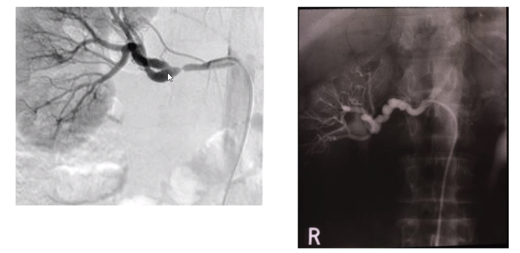

angiogram with renal artery stenosis that has since been fixed